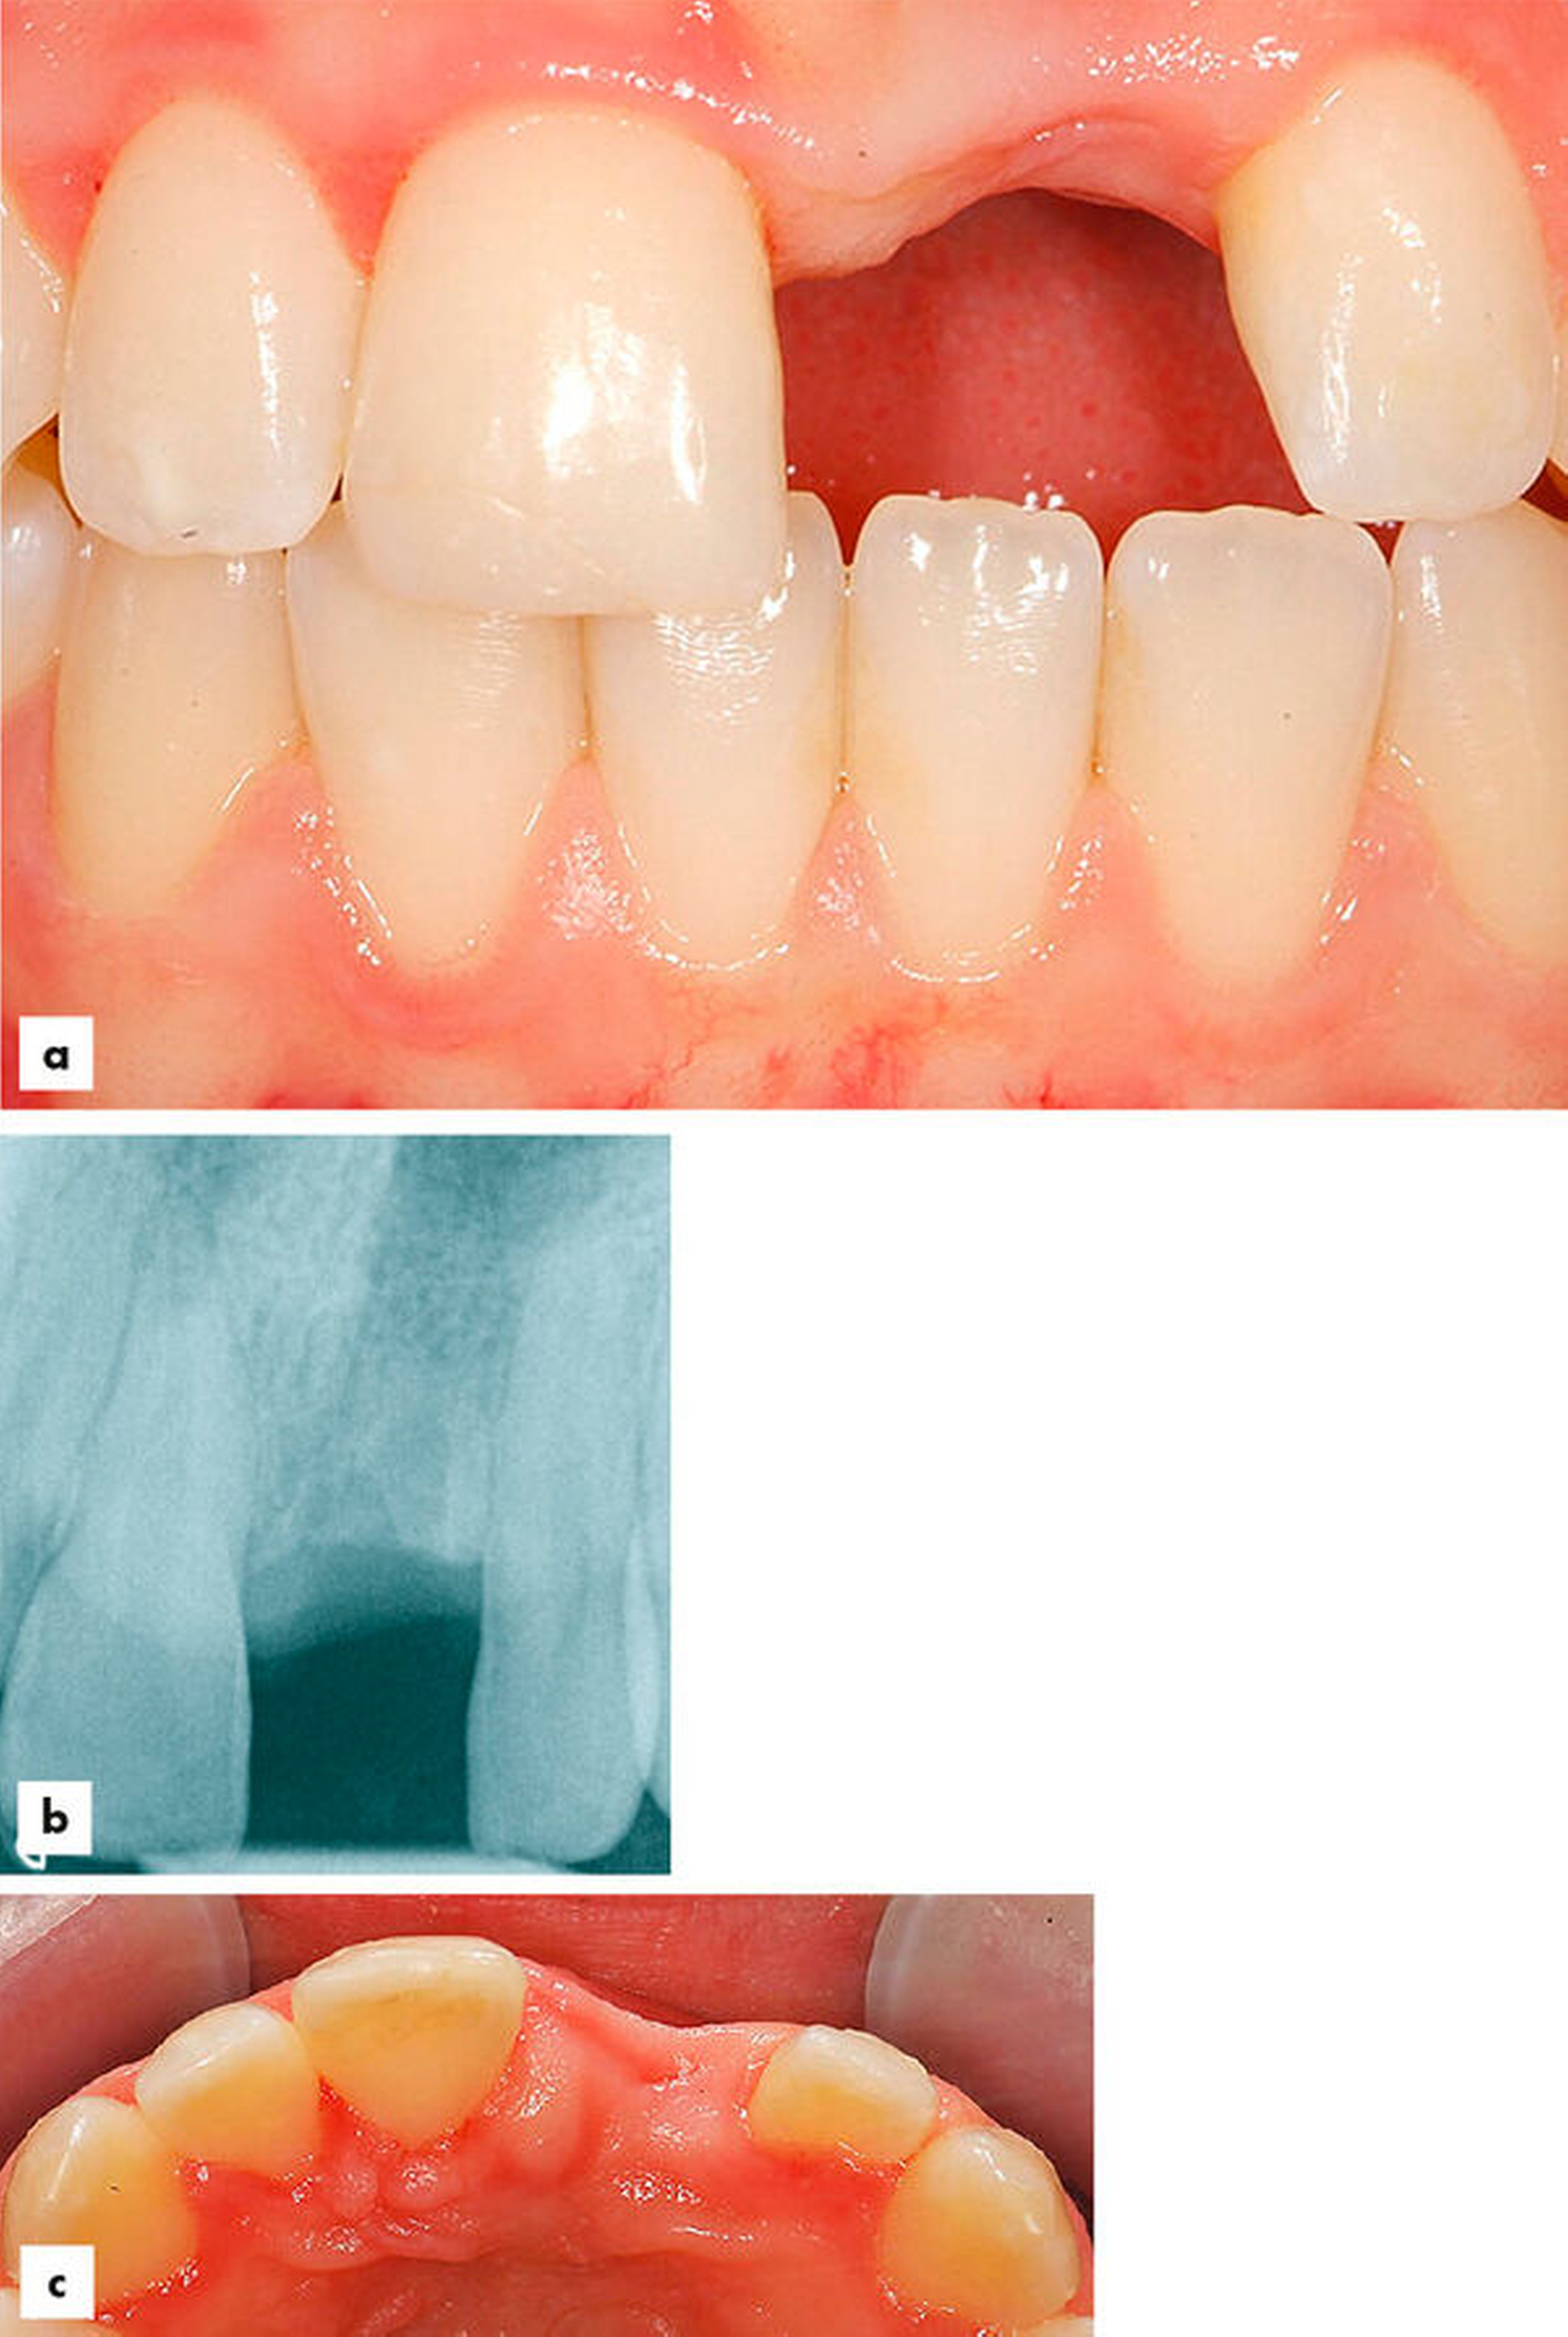

Ein 59-jähriger Mechaniker stellte sich mit frakturiertem Zahn 12 und verlorener Krone in der Poliklinik für Zahnerhaltungskunde der Klinik für Mund-, Zahn- und Kieferkrankheiten des Universitätsklinikums Heidelberg vor (Abbildungen 5a und 5b). Bei der Erhebung der allgemeinen Anamnese gab der Patient eine koronare Herzerkrankung und eine chronisch-obstruktive Lungenerkrankung (COPD) an. Er rauchte nicht, nahm ein Präparat zur Antikoagulation (Xarelto 10 mg) und bei Bedarf ein kortisonhaltiges Asthmaspray (Symbicort 160/4,5 µg/Dosis) ein. Zum Zeitpunkt der Erstvorstellung hatte der Patient keine Schmerzen, keine Zahnlockerungen und keine erhöhten Sondierungstiefen an Zahn 12. Da der Wurzelrest des Zahns 12 nach Verlust der Restauration umgehend mit provisorischem Zement abgedeckt worden war, konnte eine Reinfektion des Kanals nahezu ausgeschlossen werden. Der Röntgenbefund zeigte eine unauffällige periapikale Region und eine intraradikuläre Transluzenz im Sinne einer homogenen Wurzelkanalfüllung nach Restaurationsverlust, die bis etwa 1,0 mm vor das Foramen apikale reichte (Abbildung 5c).

Erste Phase: individueller Wurzelstift

Die wichtigsten für die R3-Technik verwendeten Materialien sind in Tabelle 2 aufgeführt.In der ersten Phase wurden die zugänglichen Oberflächen des Wurzelrests gereinigt, die Karies exkaviert und unter relativer Trockenlegung die Wurzelkanalfüllung um 5 mm gekürzt. Anschließend wurde das faserverstärkte Kompositmaterial, wie im vorherigen Fallbeispiel dargestellt, abgemessen (5 mm Wurzelkanal plus 5 mm koronaler Anteil) und mit einer Schere in der Verpackung zurechtgeschnitten. Nach Anätzen mit Phosphorsäure, Spülen und Trocknen von Wurzeloberfläche und Kanallumen des Zahns 12 erfolgte das Auftragen von Primer und Adhäsiv mit anschließender Lichthärtung. Daraufhin wurde zunächst eine kleine Menge eines fließfähigen Bulk-Fill-Komposits in den Wurzelkanal eingebracht. Im Anschluss wurde das faserverstärkte Kompositmaterial platziert und mit einer Polymerisationslampe mit speziellem Ansatz lichtgehärtet (Abbildungen 5d–5f). Aufgrund der Größe des Kanallumens wurde im vorliegenden Fall lediglich ein Strang des faserverstärkten Kompositmaterials eingebracht, bei großvolumigeren Kanälen hätten problemlos zwei bis drei Stränge fächerförmig in die Kompositmasse eingebracht und polymerisiert werden können.